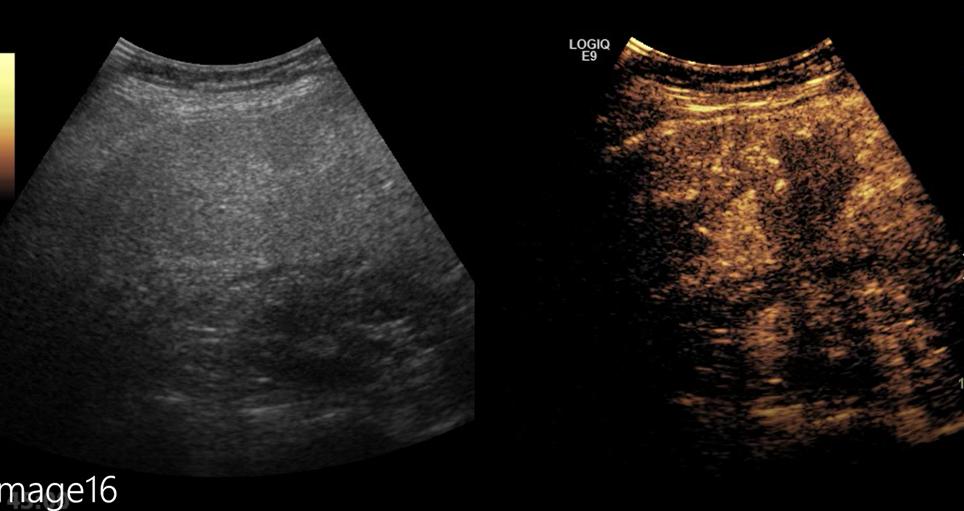

然而普通造影剂显影时间仅有3-5分钟,对于肝脏多发性病变的消融治疗,显影时间显然是不够用的,术中不但要看得准,而且还要看得远,因此超声介入组选择了肝脏特异性造影剂,利用其特有的肝脏kuffer期(肝细胞期),可以实现对转移性病灶长达30分钟的显影,使得整个手术过程都在清晰的造影显影下进行。

在肝脏特异性造影模式下行术中肝脏多发转移灶微波消融术

手术方案制定后,由胃肠外1科任双义主任及张新生副主任主刀,先进行3D腹腔镜远端胃切除术、肝边缘肿物部分切除术,随后超声(介入)科宋宇副主任上台,在肝脏特异性造影模式下进行肝脏左右叶多发深部转移灶微波消融术,术后复查造影显示,所有转移灶均已完全灭活,达到无瘤生存。手术共历时四个半小时,两周后,患者恢复良好,顺利出院。

术后超声造影显示消融区均呈无增强,提示病灶完全坏死